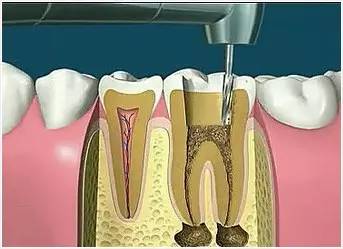

2、揭开髓腔

去净腐质和原有充填物、揭净随顶,看到整个髓底解剖结构以便后续治疗顺利进行。

4、根管预备

根管清理成形的目的是去净根管壁上的感染物,通过根管器械的切削作用去除感染的牙本质并清理根管壁细菌以利于根管充填。